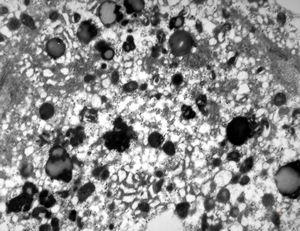

M,16y. | lipofuscin - hyperbilirubinaemia - Gilbert or Dubin-Johnson syndrome

M,17y. | lipofuscin - hyperbilirubinaemia - Gilbert or Dubin-Johnson syndrome

M,17y. | hyperbilirubinaemia - lipofuscin - Gilbert or Dubin-Johnson syndrome

F,12y. | lipofuscin - hyperbilirubinaemia - Gilbert or Dubin-Johnson syndrome